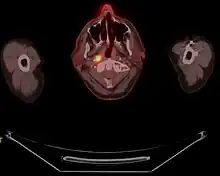

Radiation therapy uses high energy x-rays or other types of radiation aimed to prevent cancer cells from growing or kill them altogether. This kind of therapy can be administered to the patient externally or internally. With external radiation, a machine is used to send targeted radiation to the cancer site. A mesh mask is used on the patient in order to keep their head and neck still while the machine rotates to send out beams of radiation. In undergoing this kind of treatment, healthy cells may also be damaged during the process. Therefore, there are 2 other forms of radiation therapy that decreases the likelihood of damaging nearby healthy cells: intensity-modulated radiation therapy and stereotactic radiation therapy. Intensity-modulated radiation therapy (IMRT) uses 3D images of the size and shape of the tumor to then direct thin beams of radiation at different intensities from multiple angles. In stereotactic radiation therapy, radiation is aimed directly at the tumor. In this therapy, the total amount of radiation is divided into smaller doses that will be given over the course of several days.

Using radiation therapy as a cancer treatment method depends on the type and stage of cancer; however, internal and external radiation therapies can be used to treat NPC. If external radiation therapies are being aimed at the thyroid, then this could affect the way the thyroid works. For that reason, blood tests are done before and after radiation to check thyroid hormone levels.[22]